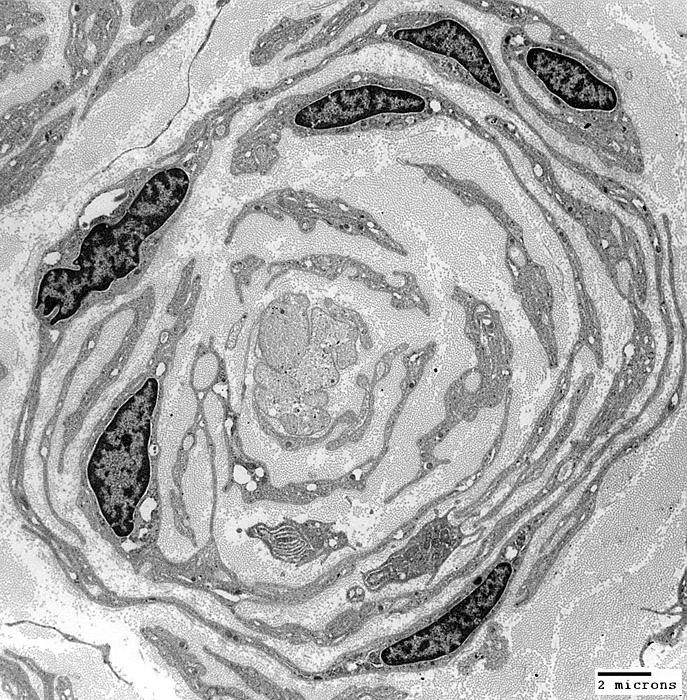

Onion Bulbs: Around demyelinated axons

From: Robert Schmidt MD

Onion bulbs, Large: Several layers surround demyelinated axons

Layers include

Schwann cell processes

Schwann cell basal lamina

Connective tissue

Outer rim: My be fibroblast process

Central axon: Unmyelinated